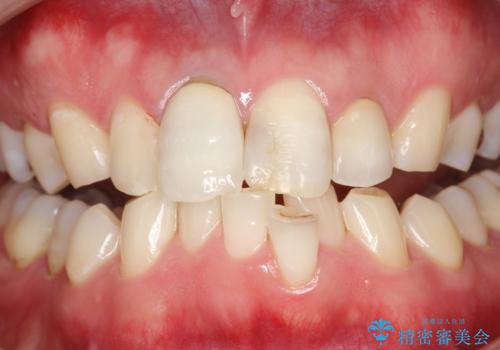

- 約3年ほど歯科医院での定期健診やクリーニングを受けてないとのことでした。全体的に歯石・着色などが付着していていたためPMTC60分コースを行いました。

分厚く歯石や着色が付着していると、汚れなのか虫歯なのかの判別がしづらい場合があります。しばらく定期健診やクリーニングを行っていない場合は、まずはしっかりと汚れを除去し、本来のご自身の歯の状態にすることで、より精密なお口の状態の診断が行えます。

PMTCによって、CRと、ご自身の歯の境目の着色などがしっかりと落とせて目立たなくなる場合と、PMTCによってしっかりとクリーニングを行うと、CR自体が古く劣化・変色などしていて目立ってくる場合があります。気になる際は詰め替えを行います。